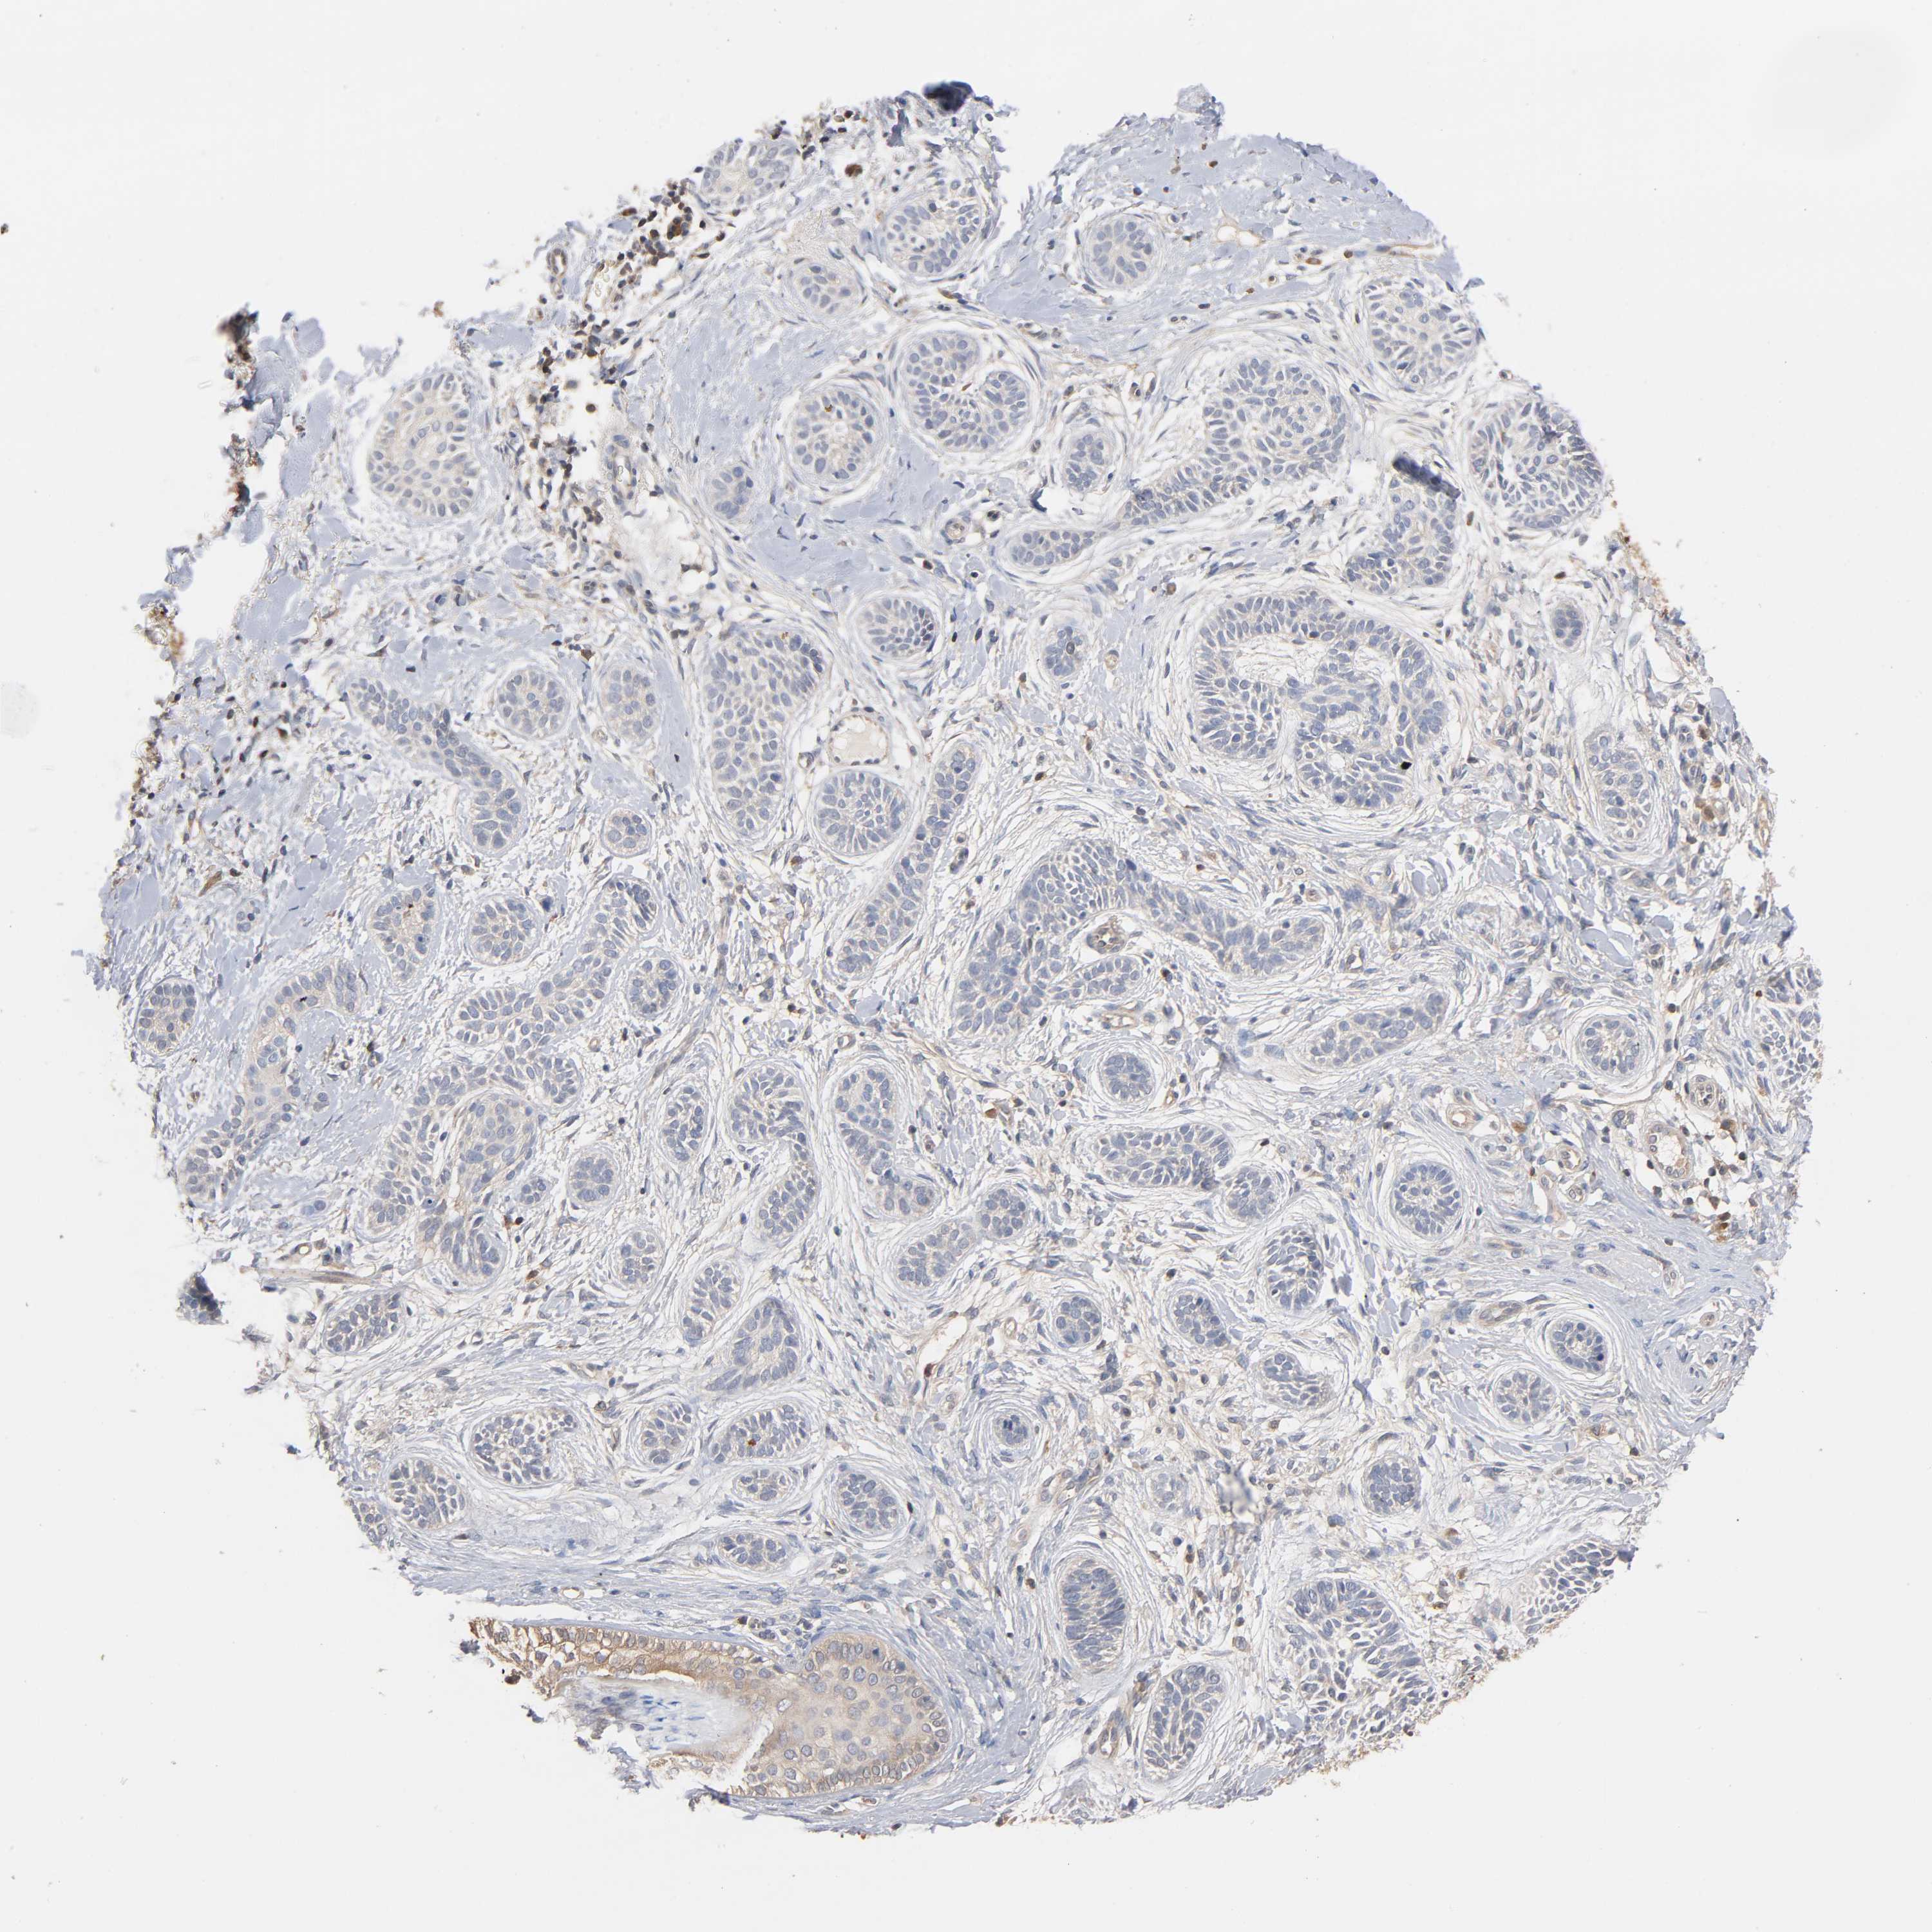

SKIN CANCER - Protein expressioni

A mouse-over function shows sample information and annotation data. Click on an image to view it in a full screen mode. Samples can be filtered based on level of antibody staining by selecting one or several of the following categories: high, medium, low and not detected. The assay and annotation is described here.

Each image is clickable and will lead to virtual microscopy that enables deeper exploration of all samples and also displays staining intensity scores, fraction scores and subcellular localization as well as patient and tissue information for each sample.

Antibody HPA004177

Staining

High

Medium

Low

Not detected

Intensity

Strong

Moderate

Weak

Negative

Quantity

>75%

75%-25%

<25%

None

Location

Nuclear

Cytoplasmic/membranous

Cytoplasmic/membranous,nuclear

Basal cell carcinoma